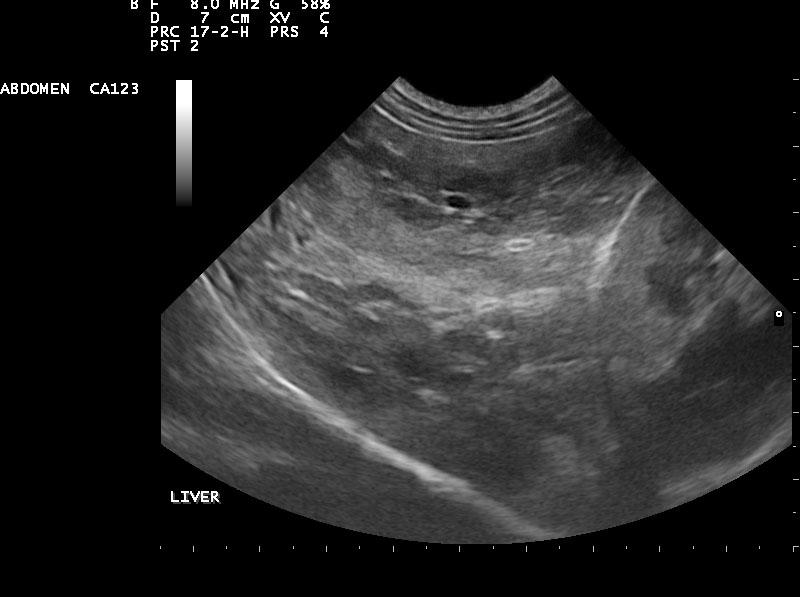

Diffuse nodular liver disease and microhepatica. The portal vein can be followed completely to its branches, but it is very tortuous and with the ascites that is seen, might be indicative of portal hypertension. This is typical cirrhosis with possible portal vein branch hypoplasia-microvascular dysplasia. The bile acids are likely very high and the clinical signs are owing to hyperammonemia. There are secondary shunts as well demonstrated by the tortuous vessels especially in the area of the pancreas where there is pancreatic edema. The lobe portal vein velocities support portal vein hypertension.